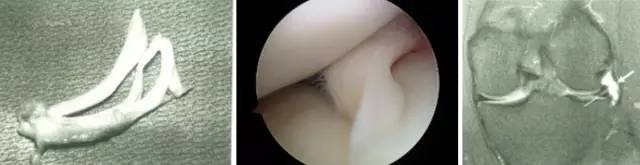

膝关节镜-半月板损伤

膝关节镜-前交叉韧带重建

膝关节镜-关节内游离体

膝关节镜/肩关节镜/踝关节镜/髋关节镜/肘关节镜